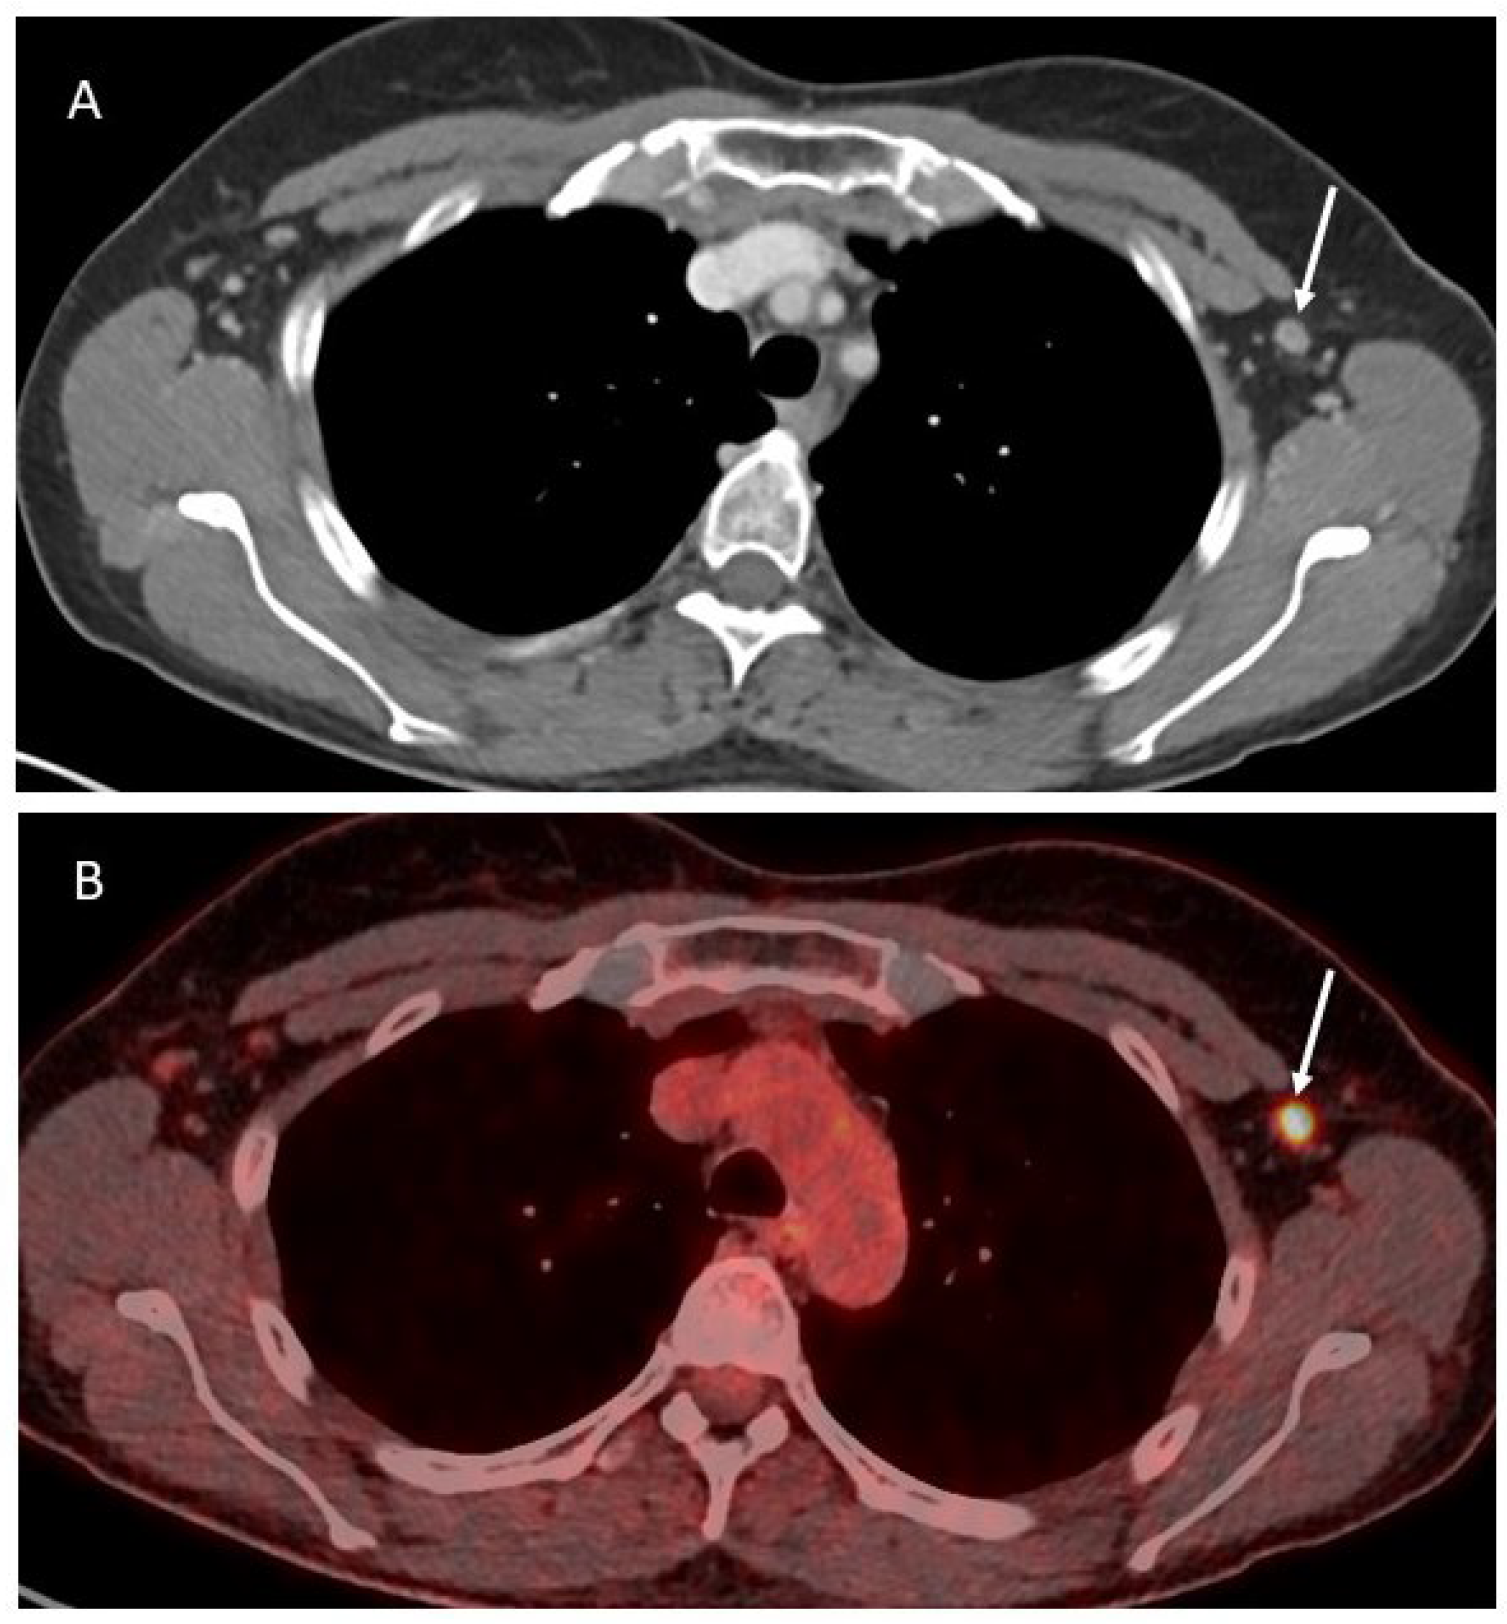

3.2. Imaging

4.2. Imaging

5.2. Imaging